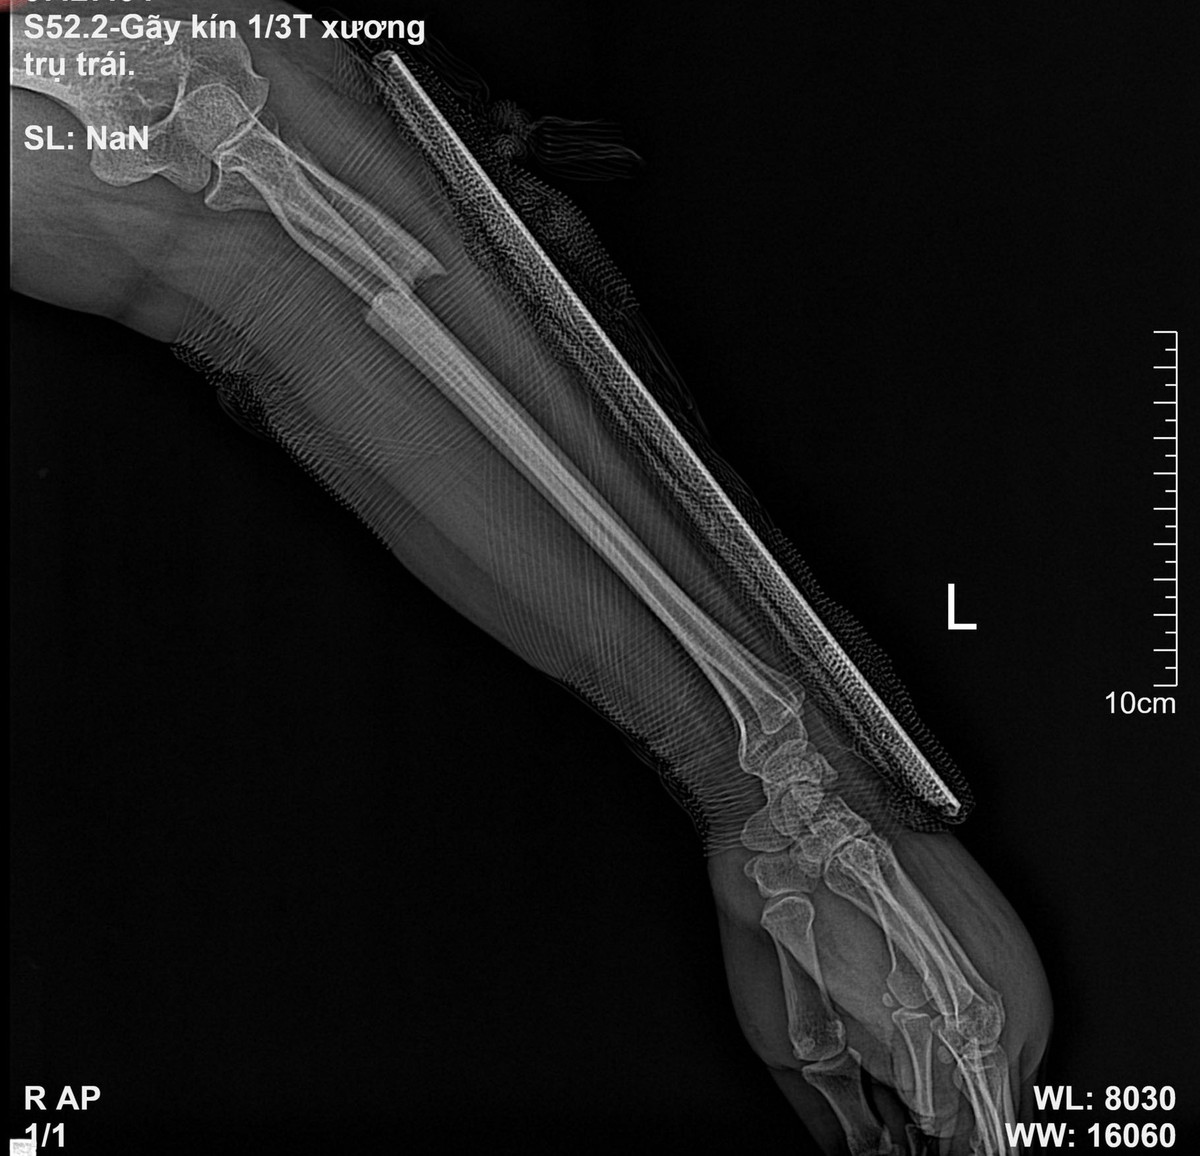

Thông tin trên Vietnamnet cho biết, 3 tuần trước khi vào viện, nữ bệnh nhân (ở Phú Thọ), bị ngã. Sau đó, người bệnh thấy đau nhiều ở cẳng tay trái. Không đến viện thăm khám, người này tự điều trị tại nhà bằng cách đắp thuốc nam. Bệnh nhân đến Bệnh viện đa khoa Hùng Vương khám trong tình trạng cẳng tay trái sưng nề, đau đớn, vận động hạn chế.

| Ảnh: Vietnamnet. |

Kết quả chụp X-quang cho thấy, hình ảnh gãy 1/3 trên xương trụ tay trái, các bác sĩ chỉ định mổ kết hợp xương. Sau khi điều trị, bệnh nhân ổn định và được xuất viện.